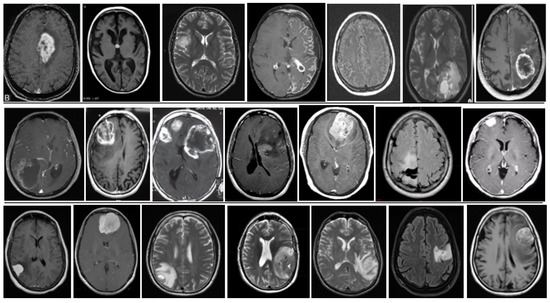

5. Database and Dataset

5.1. DataBase Collection

5.2. Database Augmentation

- Dataset generation and expanding an existing dataset (Figure 5)